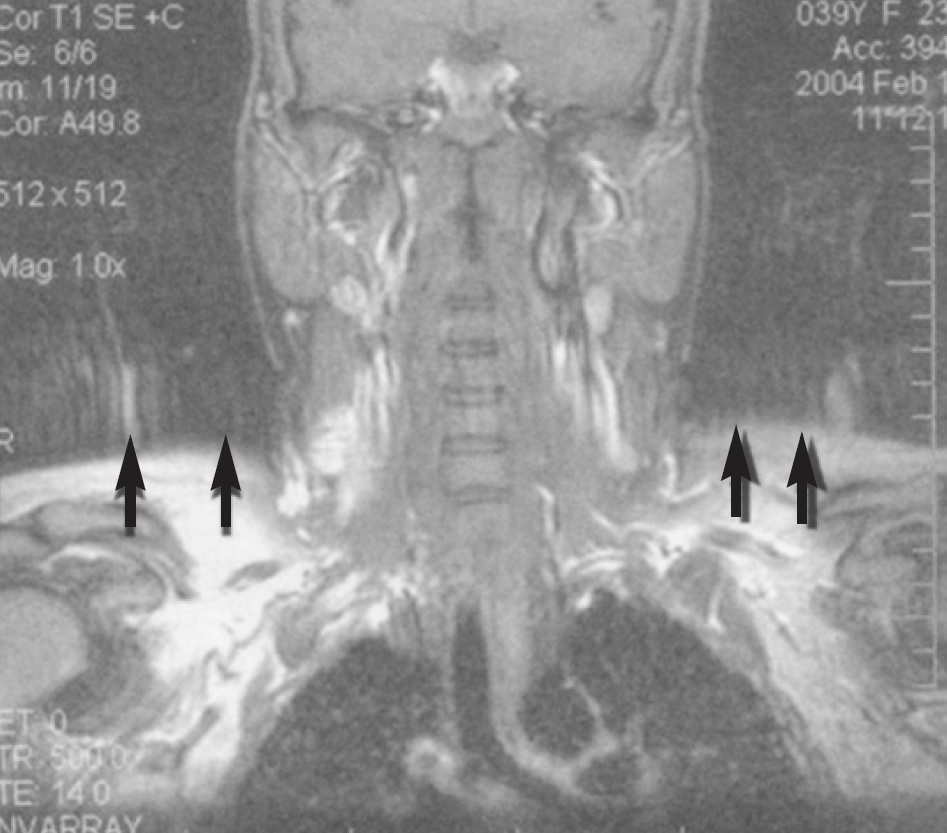

MRI运动伪影示例MRI运动伪影:患者在扫描过程中的运动导致图像出现模糊、重影和条纹等伪影